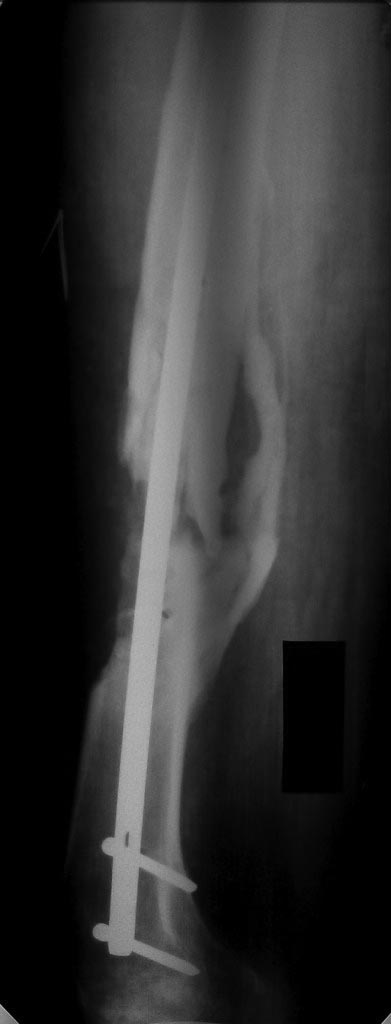

Уважаемые коллеги! Помогите определиться с тактикой лечения у молодого

пациента.

Молодой парень, 25лет. Травму получил в ноябре 2012 года, ДТП.Оперирован

в сельской больнице, остеосинтез перелома бедренной кости пластиной и

АВФ на голень с этой стороны, наложена гипсовая повязка коксит на 3

месяца. В момент госпитализации разгибательная контрактура коленного

сустава (движения в коленном суставе сгибание 10 градусов) 02.07.2013

рентгенапаратом. Как быть с ложным суставом голени?

1. БИОС голени- оптимальный вариант,но при отсутствии желаемого сгибания

в коленном суставе сможем ли мы сделать( Наш опыт - всего 30 операций по

БИОСу)

2ЧКДО по Илизарову( после АВФ)